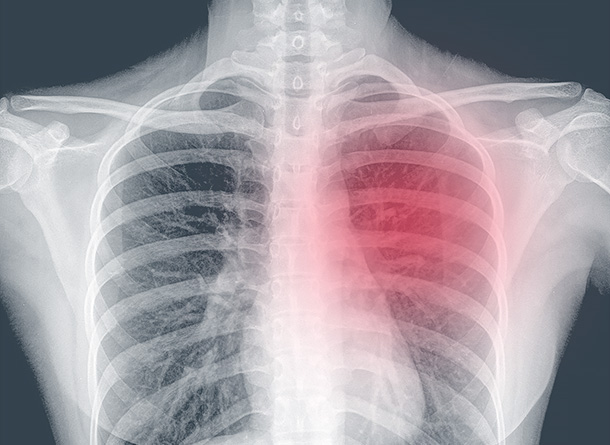

Neural network reads medical scans without human input

A complex solution automates cholesterol plaque detection in artery scan videos, helps calculate the intima-media thickness, and makes analysts work faster - all using the computer vision. The artery wall thickness is calculated with 95% accuracy, potential plaque detection is 80% correct. As a result of the project, the solution price became more competitive due to savings on expensive human resources.

Anomalies can be detected in any data. For example, integration with a medical video scanner makes it possible to rapidly find several informative frames and reduce the probability of medical error, as well as speeding up the work. In logistics and shipping, anomaly prediction prevents collisions and flooding of ships, and increases the safety of transportation.